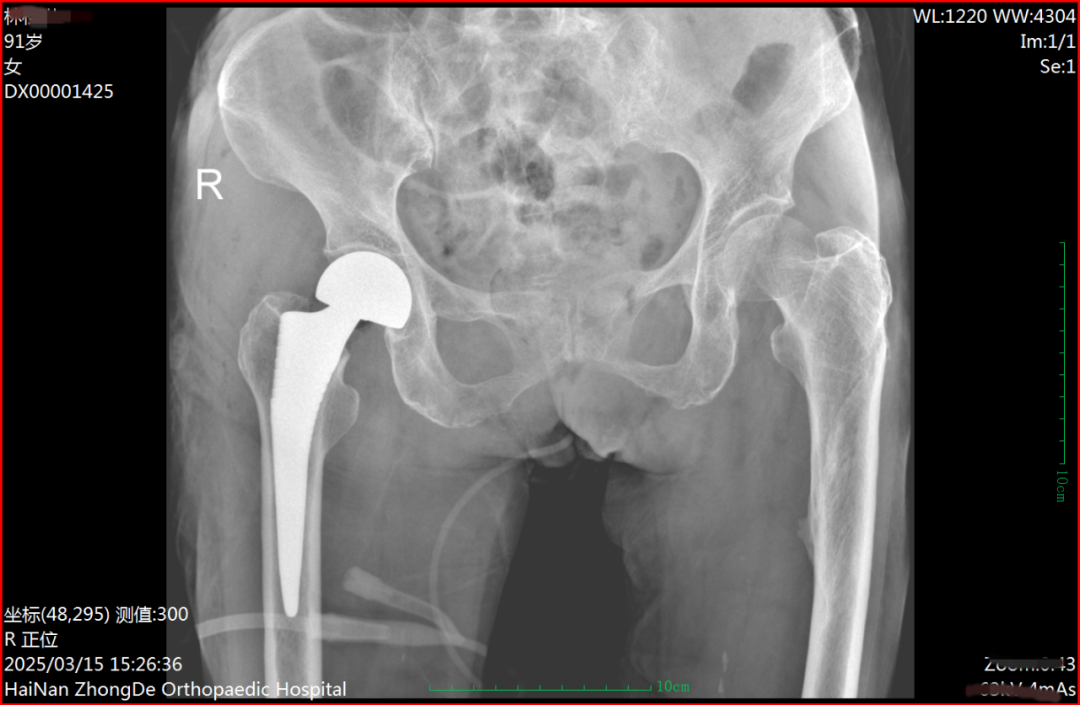

术后DR片

术后患者转入重症监护室,由骨科、老年病科和神经内科团队联合监护。目前,患者生命体征平稳,骨折部位固定良好,未出现感染等并发症。康复团队已制定个性化康复计划,帮助患者逐步恢复功能。家属们对医院的精湛医术和医护人员无微不至的关怀给予了极高的评价和由衷的称赞。